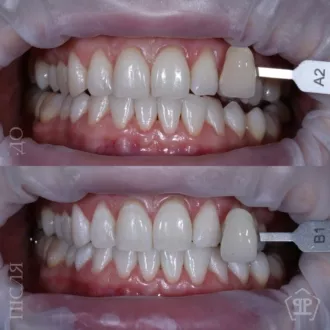

Безопасное профессиональное отбеливание Beyond Polus